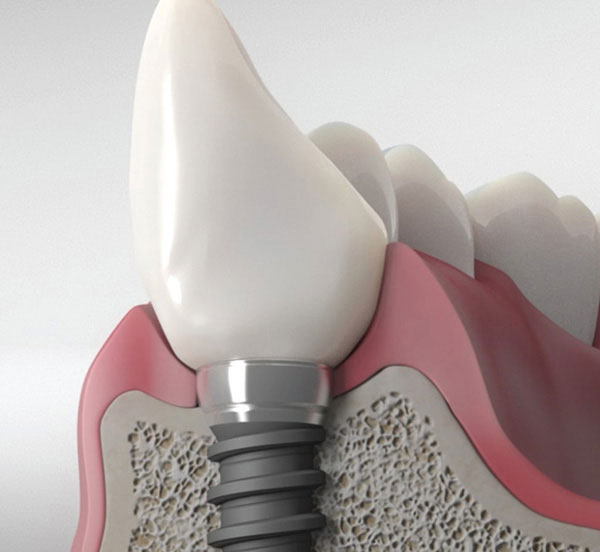

Q. I have dental implants. Can I have TPT?

A. Yes, TPT can be done with implants as well. With the two wavelength lasers, there is no danger of thermal damage to the surrounding bone and no significant alterations of the implant surface. Lightwalker laser is unique that it has both Er:Yag and ND:Yag, while most lasers only have one of the two. This makes the Lightwalker unique in its ability to safely perform TPT on implants.